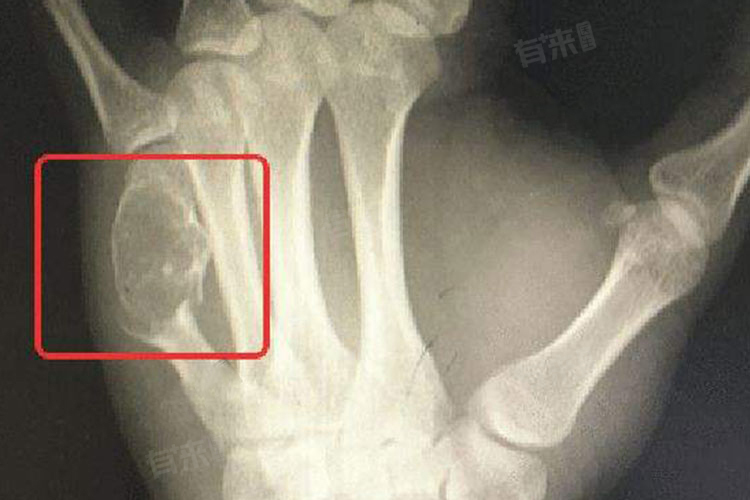

- X射线检查:是诊断骨癌的常用手段,可以初步了解骨质的大致状况,如有无骨质缺损、异常增生或畸形等,在骨癌中,X射线可能显示出膨胀性生长的骨破坏、边缘毛刺感、日光照射征等特征性表现。